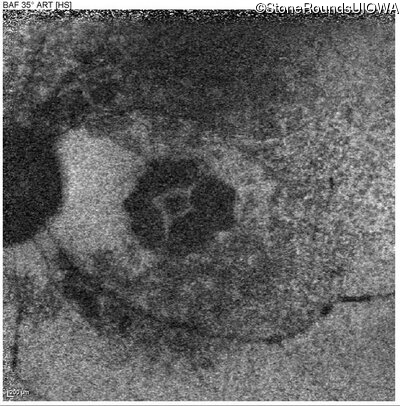

Blue Autofluorescence - Right - 20/25

Exemplar